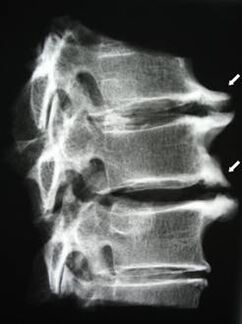

На пачатковых стадыях астэахандроз выяўляецца з дапамогай МРТ. Пазней паталогію можна дыягнаставаць з дапамогай рэнтгенаграфіі. На рэнтгенаграмах шыйнага аддзела хрыбетніка прыкметныя памяншэнне адлегласці паміж пазванкамі, паталагічныя змены фасеткавых суставаў, остеофитоз.

| Шыйны астэахандроз | З'яўленне паталагічных змен у адным або некалькіх спінна-рухальных сегментах. Парушэнне рухомасці пазваночніка, развіццё миофасциальных болевых сіндромаў і зашчымленне спіннамазгавых карэньчыкаў. | Боль, парэстэзіі і рухальныя парушэнні ў шыйным аддзеле, якія распаўсюджваюцца на патыліцу і верхнія канечнасці. Выяўленне характэрных змяненняў у пазваночніку на МРТ і рэнтгенаграме (остеофиты, памяншэнне адлегласці паміж пазванкамі, прыкметы паразы межпозвонковых суставаў) |